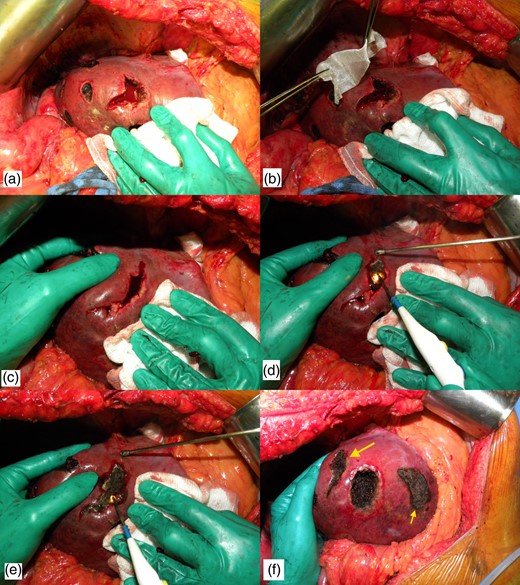

After identification of the lesion by inspection and intraoperative ultrasonography, Glisson's capsule is marked with eletrocautery 2 cm away from the tumor margin. The marked area is checked by ultrasonography to ascertain surgical margin right before liver transection. Hemihepatic ischemia or Pringle maneuver can be applied, according to location of the tumor. Parenchymal transection is performed with bipolar forceps or the crush technique. After removal of the tumor, a large and deep defect is produced, often with minor or major bleeding. The technique consists of filling the defect with any absorbable hemostatic tissue available, such as Surgicel (Ethicon, Cincinnati, OH, USA), and wait until this hemostatic tissue is imbibed with blood. The cautery is put at maximum power in coagulate mode and the blood is cooked until a crust is formed (Fig. 1).

Technique of bleeding control. (a) Intraoperative photograph after enucleating a deep located metastasis. Note that there is a profuse bleeding. (b) Hemostatic tissue is inserted inside the defect. (c) Hemostatic tissue is imbibed with blood and liver borders are brought together with manual compression. (d) The cautery is put at maximum power in coagulate mode and the blood is cooked until a crust is formed. (e) The lateral compression is released and some residual bleeding is controlled with cautery. (f) Final view after the use of the technique (larger arrow). Note that another enucleated area was controlled with the same technique (smaller arrow).